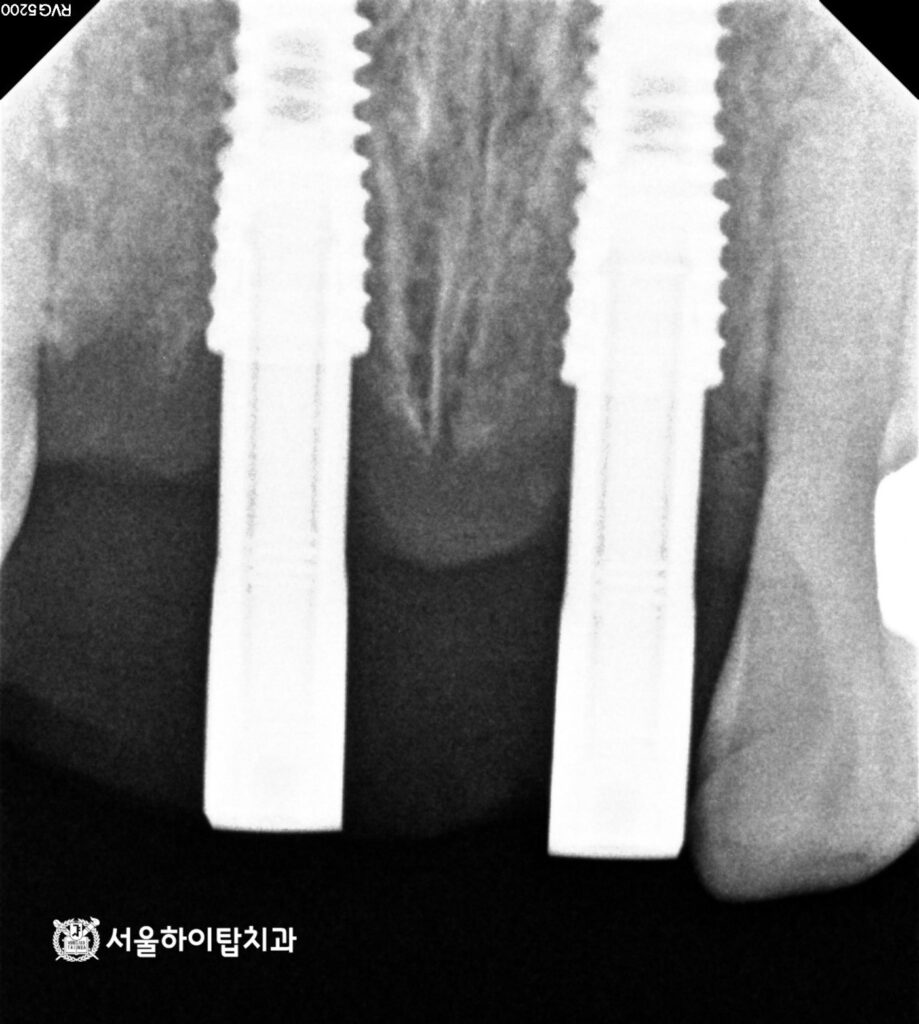

2. 정밀한 CT 모의 식립

현재는 치관이 완전히 파절된 상태이며,

치조골 소실이 동반되어 있습니다.

따라서 보존적 치료만으로는

장기 예후를 기대하기 어렵습니다.

이러한 경우에는 발치 후

골 재생 및 임플란트를 계획하는 것이

기능, 심미 회복 측면에서

합리적인 접근입니다.

이에 따라, 픽스처가 심어질 위치를

앞선 CT를 통해 사전에 확인하고,

잔존골의 높이, 밀도, 두께 등을

면밀하게 분석합니다.

3. 수술 완료

시뮬레이션에 따라

정확한 위치이 안전하게

픽스처각 심겨진 모습입니다.

사진을 보면 두 개의 픽스처만

식립된 것을 확인할 수 있는데,

이는 전치부에 해부학적 구조와

골 형태를 고려한 결과입니다.

치조골 폭이 좁고, 치은라인이

중요한 부위이기 때문에

불필요하게 많은 임플란트를 심기보다는

기능 안정성과 심미 조화를 동시에

확보할 수 있는 최소 개수를

선택하는 것이 원칙입니다.

만수동 치과 에서 남은 한 자리는

폰틱(가짜치아)으로

대체될 것으로 보입니다.